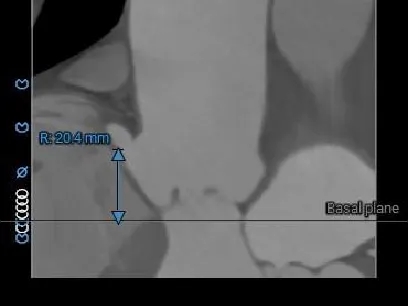

瓣上结构测量

SUPRA-2MM

SUPRA-4MM

周长76.4mm

周长径24.3mm

周长77.5mm

周长径24.7mm

SUPRA-6MM

SUPRA-8MM

周长83.4mm

周长径26.6mm

周长86.4mm

周长径27.5mm

根部整体锚定空间有限,瓣膜锚定难度大。